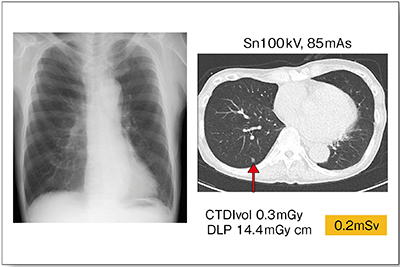

症例1は,60歳代,男性。胸部単純X線写真では異常は認められないが,実効線量0.2mSvの超低線量CTにて微小病変が認められた(図1↑)。胸部単純X線写真では検出が困難な,臓器に隠れた領域の病変検出能は,CTの方がかなり優れている。CTDIvol 0.3mGyと低被ばくでありながら,このような良好な画像が得られることを考えると,将来的には超低線量CTにて胸部のスクリーニングを行う時代が来ると思われる。

図1 症例1:臓器に隠れた微小病変の検出